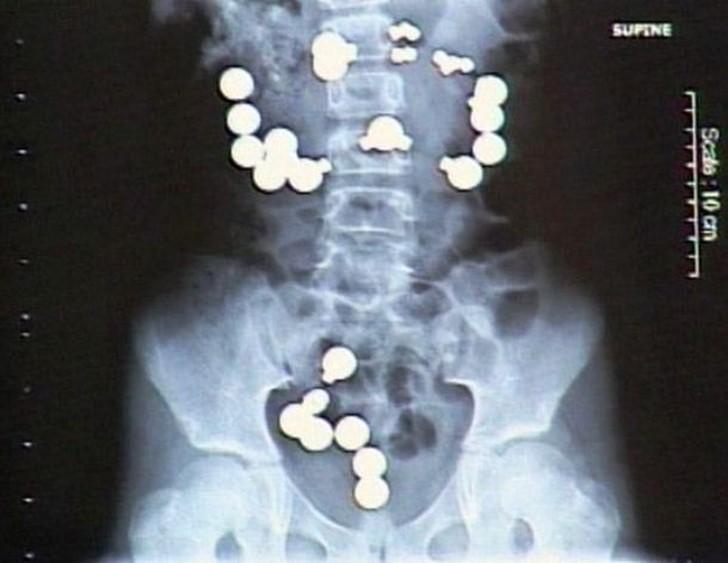

5. Магниты.